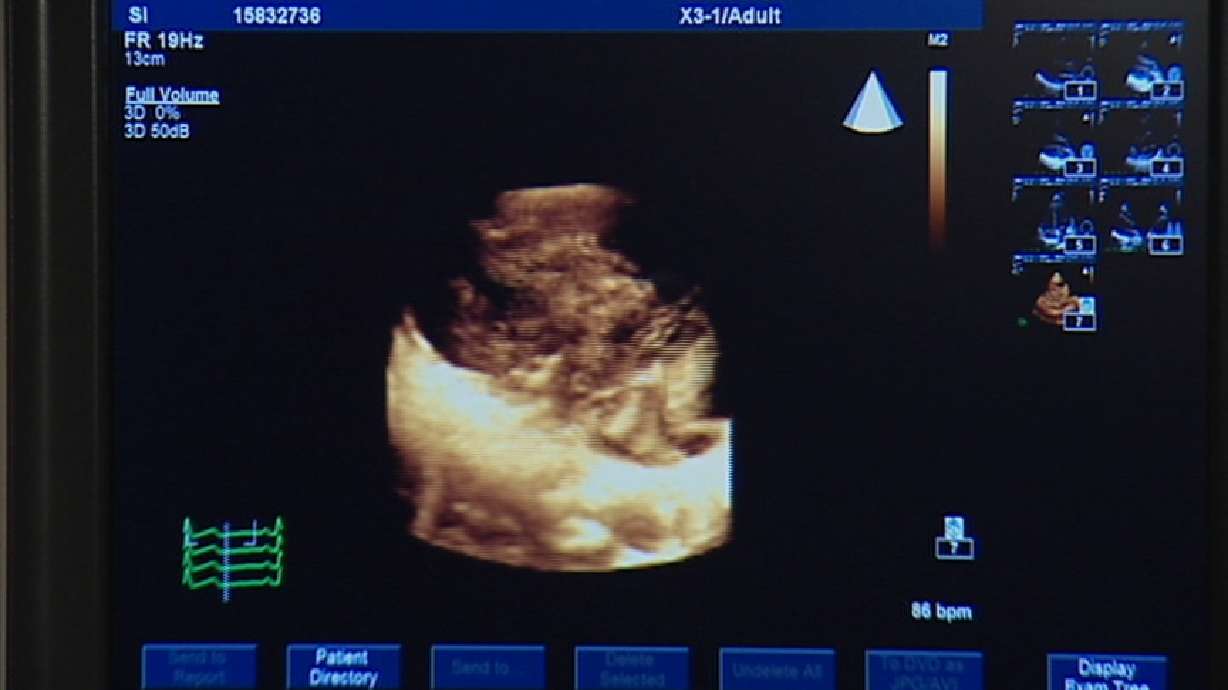

Ed Yeates ReportingPhysicians have unwrapped some new 3D technology to search out subtle problems of the heart that often go undetected. The harmless non-invasive tool is revealing some things that, up until now, required driving an invasive catheter into the heart.

In 2-D, this is about all you can see of the left ventricle of the heart. But in three dimension, all the detail comes out, including what is affectionately called the fish lip movement of the valve. Jeff certainly could see the difference.

From the bottom looking up, to the top looking down, and rotating, the 3-D moves around and through and into areas sometimes hiding subtle changes or damage. And it's all in REAL time.

Using the same technology, researchers can also set up parameters to literally map all the intricate movements of the heart, even the kind of electrical movements requiring positive and negative charges to and from the heart muscle - which sometimes get out of whack - causing an irregular or erratic heart rhythm.

Kevin Whitehead, M.D., University of Utah Cardiologist: "What an advantage to see all of the walls of the heart beating at the same time in one view and know where the areas are that need to be sped up to catch up with the rest of the heart and beat in a more coordinated fashion."

The pressure of fluid movements to and from the heart are shown in colors. It also shows valve performance - the flexing of the heart muscle - even hypertension in the lungs.